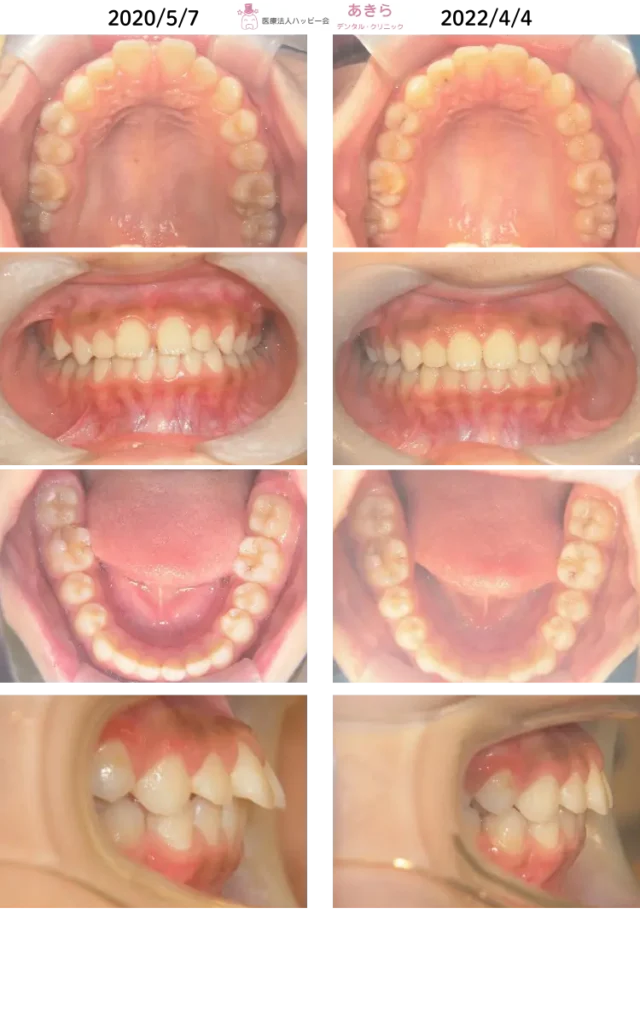

SH療法

SH療法-症例-No.012-外傷歯を伴う叢生(凸凹)の矯正症例

山形市の歯医者「あきらデンタル・クリニック」のSH療法の症例をご紹介します。 SH… -